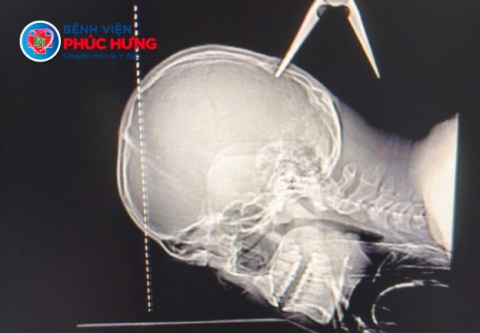

Vừa qua – Khoa Cấp cứu và Khoa Ngoại Chấn thương Bệnh viện Phúc Hưng vừa tiếp nhận và xử trí thành công một trường hợp chấn thương đầu nguy kịch, khi bệnh nhân V.H.H. được đưa vào viện với một dị vật kim loại sắc nhọn găm sâu vào vùng đỉnh đầu, tạo vết thương hở và tiềm ẩn nhiều rủi ro đe dọa tính mạng.

Theo các bác sĩ chuyên khoa, vị trí dị vật đâm vào nằm ngay vùng đỉnh sọ – khu vực có nhiều mạch máu lớn và cấu trúc thần kinh quan trọng, bất kỳ sai sót nào trong thao tác xử trí đều có thể gây xuất huyết nội sọ, tổn thương nhu mô não hoặc để lại di chứng thần kinh nặng nề.

Theo Ths.Bs Nguyễn Hoàng Lân- Bác sĩ Ngoại Chấn thương đánh giá dị vật găm sâu khoảng 1,5cm, đủ để:

- Gây chảy máu ồ ạt nếu làm tổn thương các mạch máu lớn đang được dị vật “chẹn” lại.

- Tác động trực tiếp đến nhu mô não, nguy cơ gây tổn thương vĩnh viễn hoặc tử vong.

Đặc biệt, bác sĩ nhấn mạnh: Việc rự ý rút dị vật tại hiện trường có thể khiến bệnh nhân tử vong ngay lập tức do mất máu không kiểm soát.